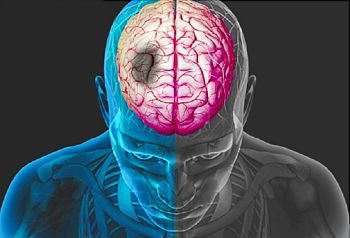

Stroke: Causes, Symptoms, and Recovery What is stroke? HEMATOMA ENLARGEMENT Intracerebral...

Hemorrhagic Stroke Diagnosis and evaluation Intracerebral hemorrhage (ICH) (Doctor only)...

What Is A Stroke? – Narration and Animation Intracerebral hemorrhage (ICH)...